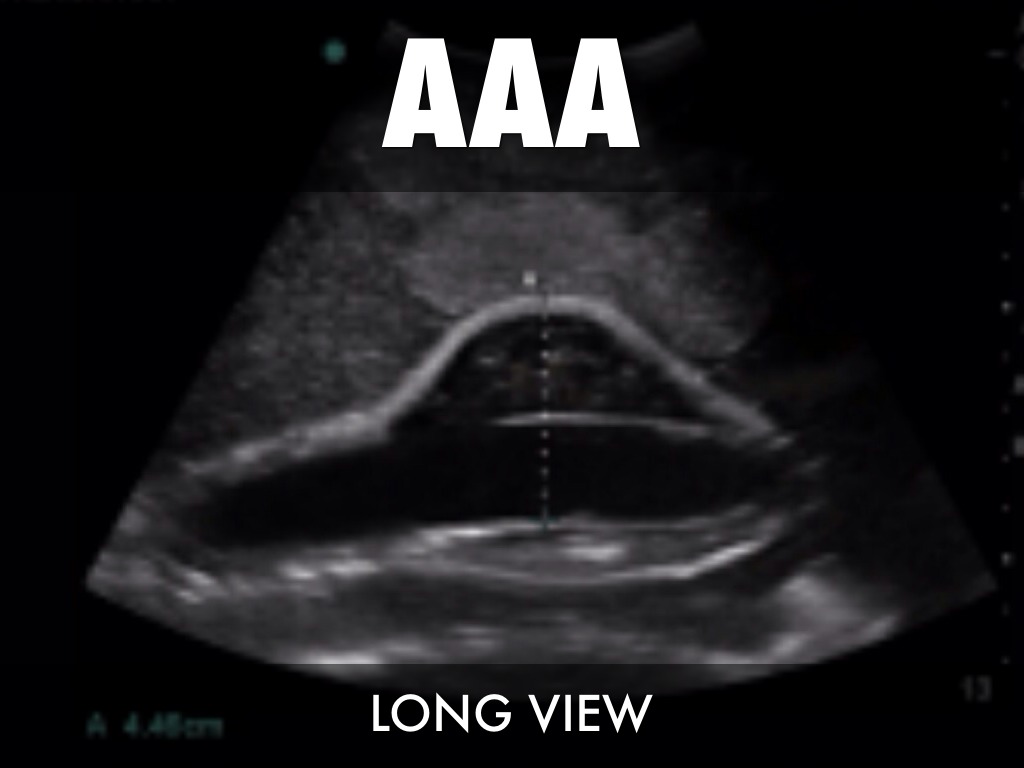

AAA

LONG VIEW